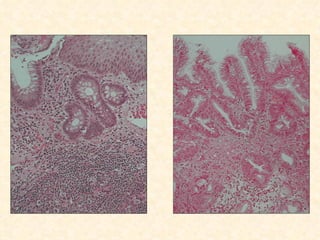

Esôfago de Barret

Refluxo GE recorrente e prolongado

Inflamação

Ulceração

Cura por reepitelização e crescimento

de células pluripotentes imaturas

ph no lúmem do esôfago distal causa diferenciação

Da mucosa para epitélio intestinal

Esôfago de Barret Refluxo GE recorrente e prolongado Inflamação Ulceração Cura por reepitelização e crescimento de células pluripotentes imaturas ph no lúmem do esôfago distal causa diferenciação Da mucosa para epitélio intestinal